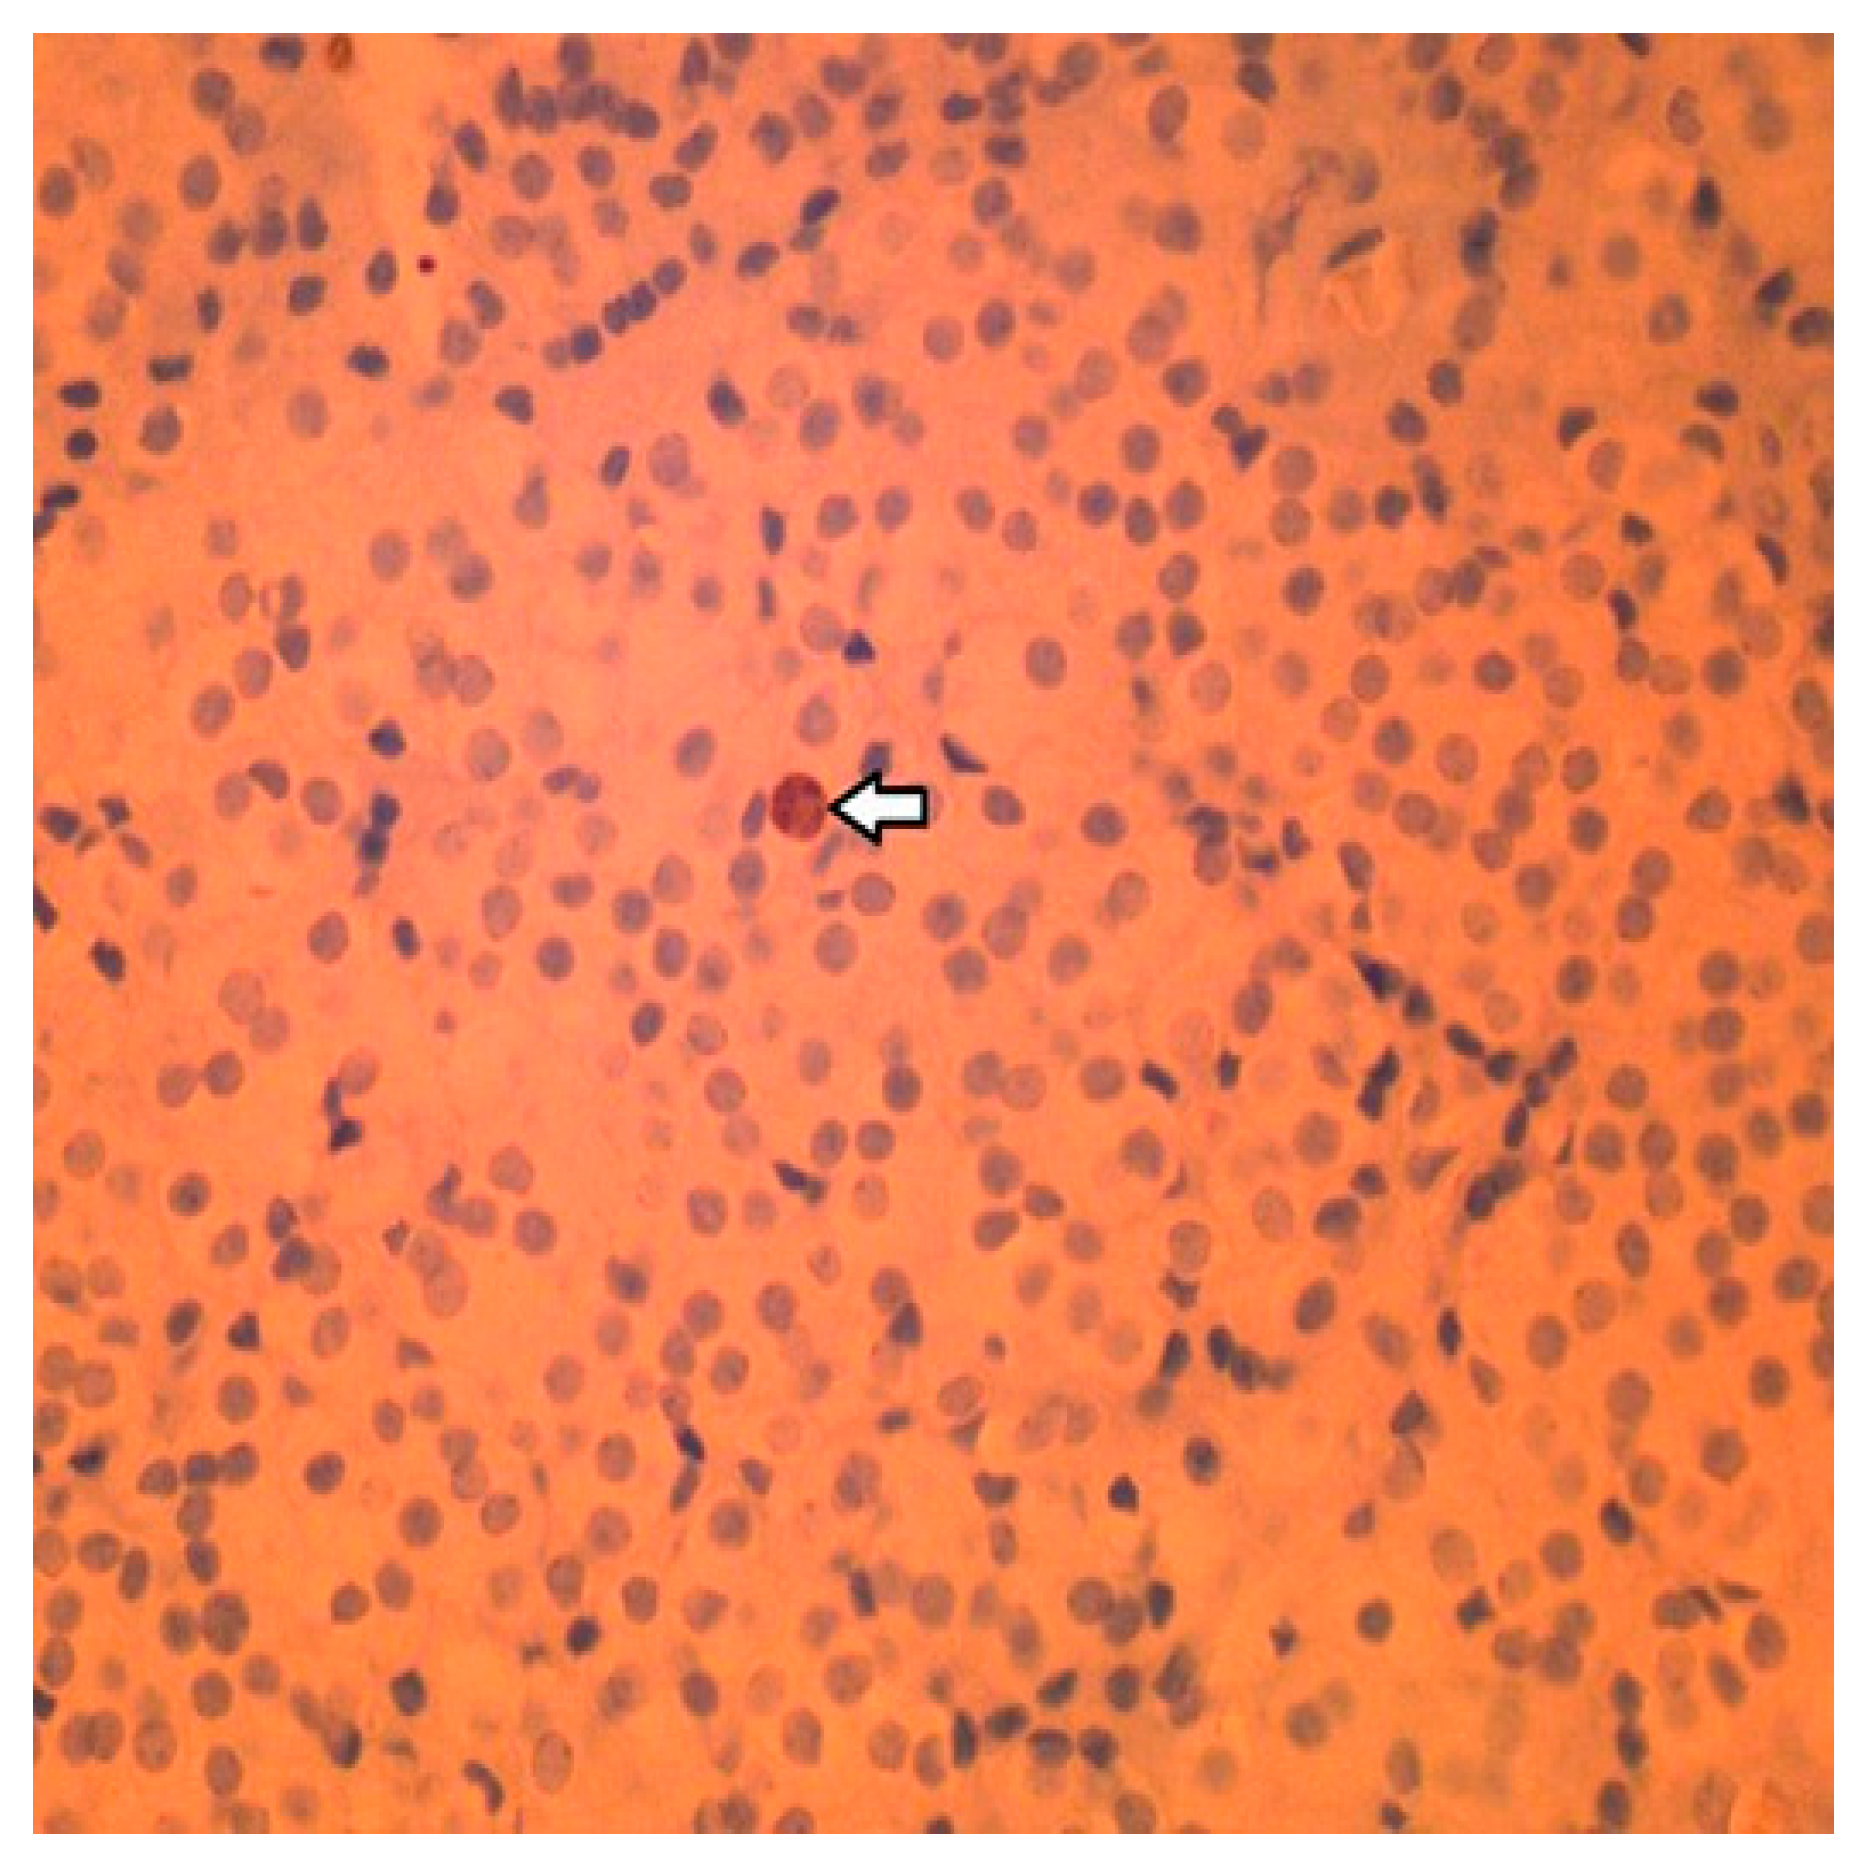

2.4. Histology